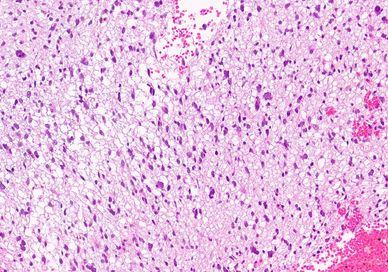

Histologic sections show a cellular neoplasm with moderate atypia/ pleomorphism.

No significant mitotic activity or areas of necrosis are identified.